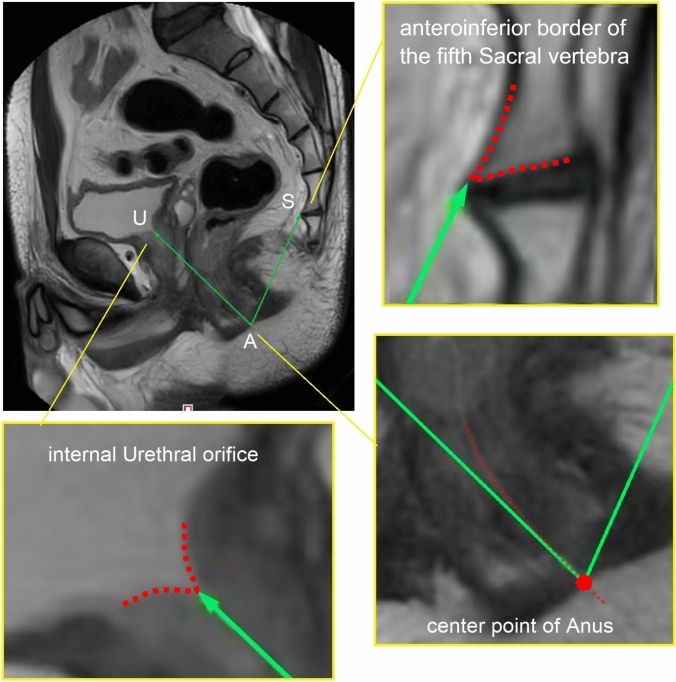

Methods: A total of 264 male patients who underwent total mesorectal excision (TME) due to primary rectal cancer located in the mid and low rectum (distal tumor margin distance from the anal verge ≤ 7 cm) were retrospectively included in the study. An angle SAU° [formed by two lines: line 1 (connecting the anteroinferior border of the fifth sacral vertebra and center point of anus) and line 2 (connecting internal urethral orifice and center point of anus)] was measured using the built-in software of MRI for every patient. The patients were categorized into four groups according to the angle SAU° and BMI. The operative time, estimated blood loss, TME quality, and anastomotic leakage (AL) were compared between group 1 and group 2 as well as between group 3 and group 4.